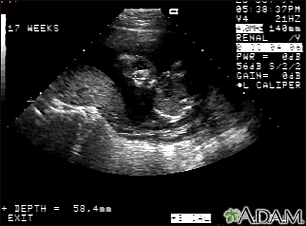

Ultrasound, normal fetus - faceBackUltrasound, normal fetus - faceThis is a normal ultrasound of the fetus performed at 17 weeks gestation. The fetal face can be seen in the middle of the screen. The head is tilted left toward the placenta, which can be seen as a mound in the left of the ultrasound image. Both eyes are visible, and the area of white within the eye is the lens. Other facial features, such as the nose and mouth, are also visible. E-mail FormEmail ResultsName:Email address:Recipients Name:Recipients address:Message: